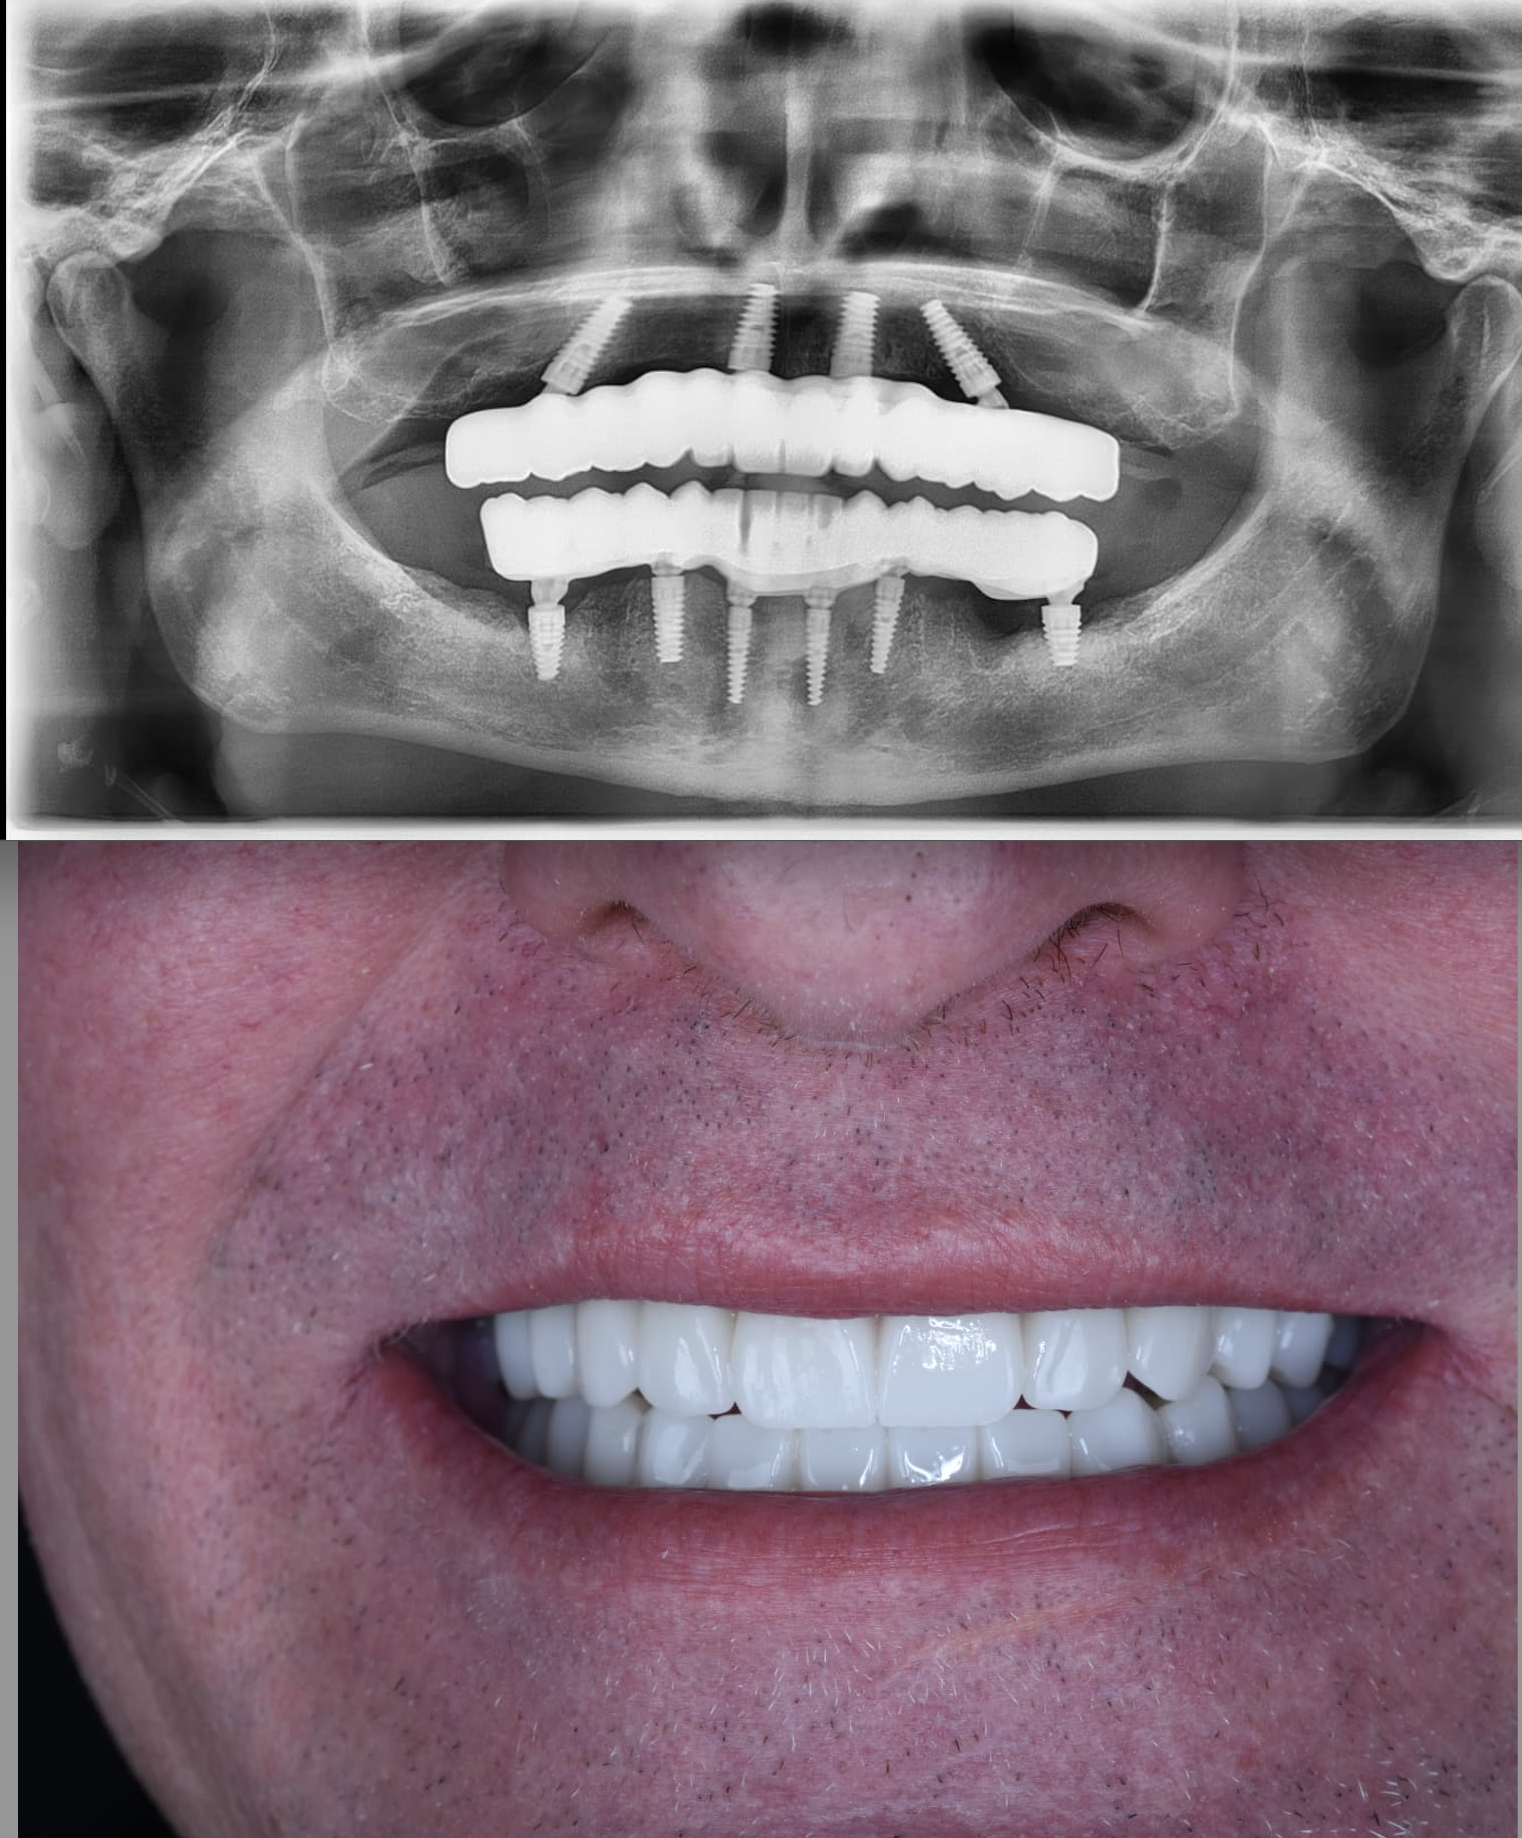

Our patient from Minnesota, USA, reached our clinic with severe bone loss issues. Thanks to the ZAGA Concept, they regained new and fixed teeth in just 24 hours using zygomatic implants.

James Erickson

2026 Minnesota, USA